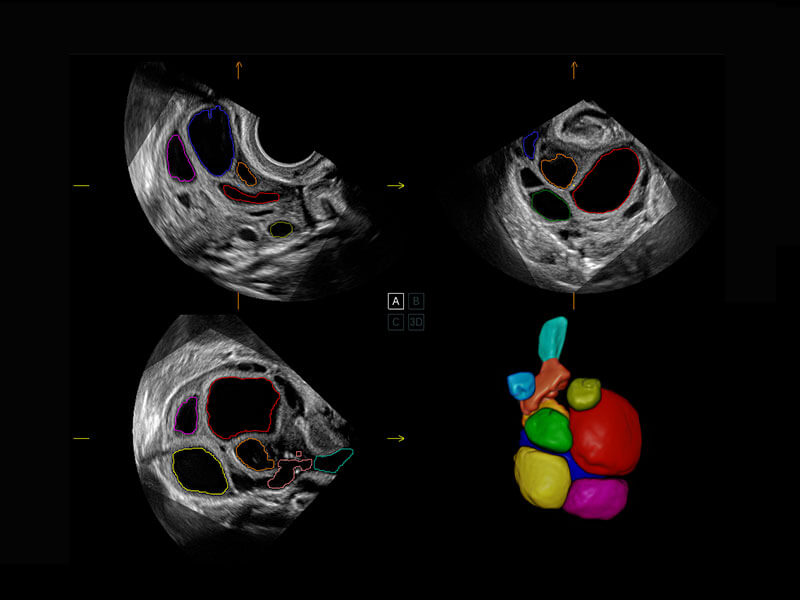

• 新生儿心脏